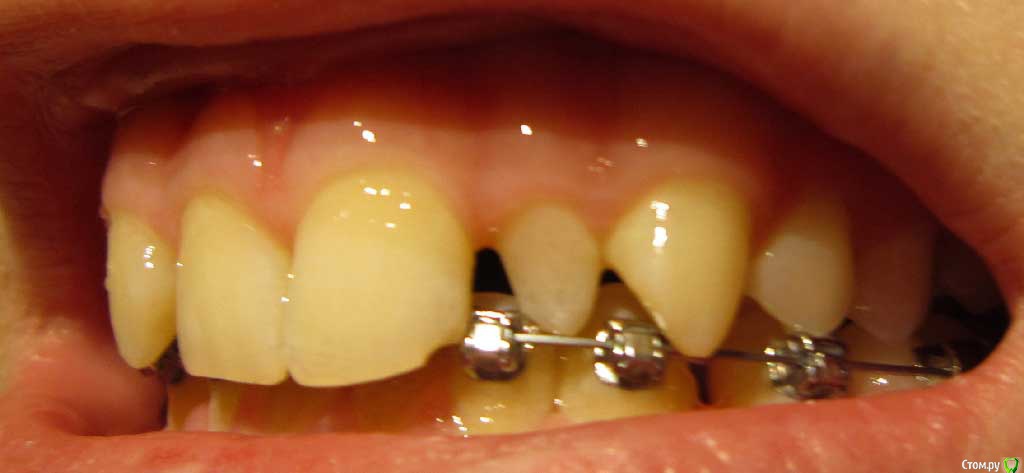

Сейчас мне 17 лет. На лечении у ортодонта с августа 2013 года. Удалили молочные пятерки и стали сдвигать шестерки к передним зубам. На верхнюю челюсть она ставить брекеты не стала. Осенью 14 года врач ушла в декрет.

Пришел новый врач который предложил все сделать несколько иначе: поставить брекеты на обе челюсти, все выравнять и освободить место под будущие импланты: вместо пятерок снизу и второго слева резца сверху -, а пока на их место поставить коронки. Также врач назвал сроки: около 1 года.

Сверху слева отсутствует зачаток второго резца, вместо него находится клык и молочный зуб левее. Внизу нет зачатков пятерок.